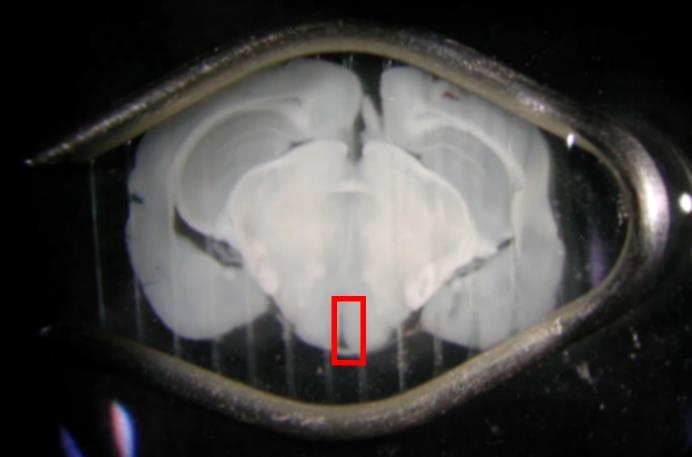

安楽死させたマウスから脳を取り出し、マイクロスライサーという装置で0.15mmの厚さに切ってから、その脳切片を動かぬように固定します(図1)。

脳室表面の上衣細胞に生えている毛(線毛)(図2)が1秒間に25回ほど往復運動しているのを顕微鏡で観察しながら動画を撮影し、メチル水銀を投与して効果を調べました。